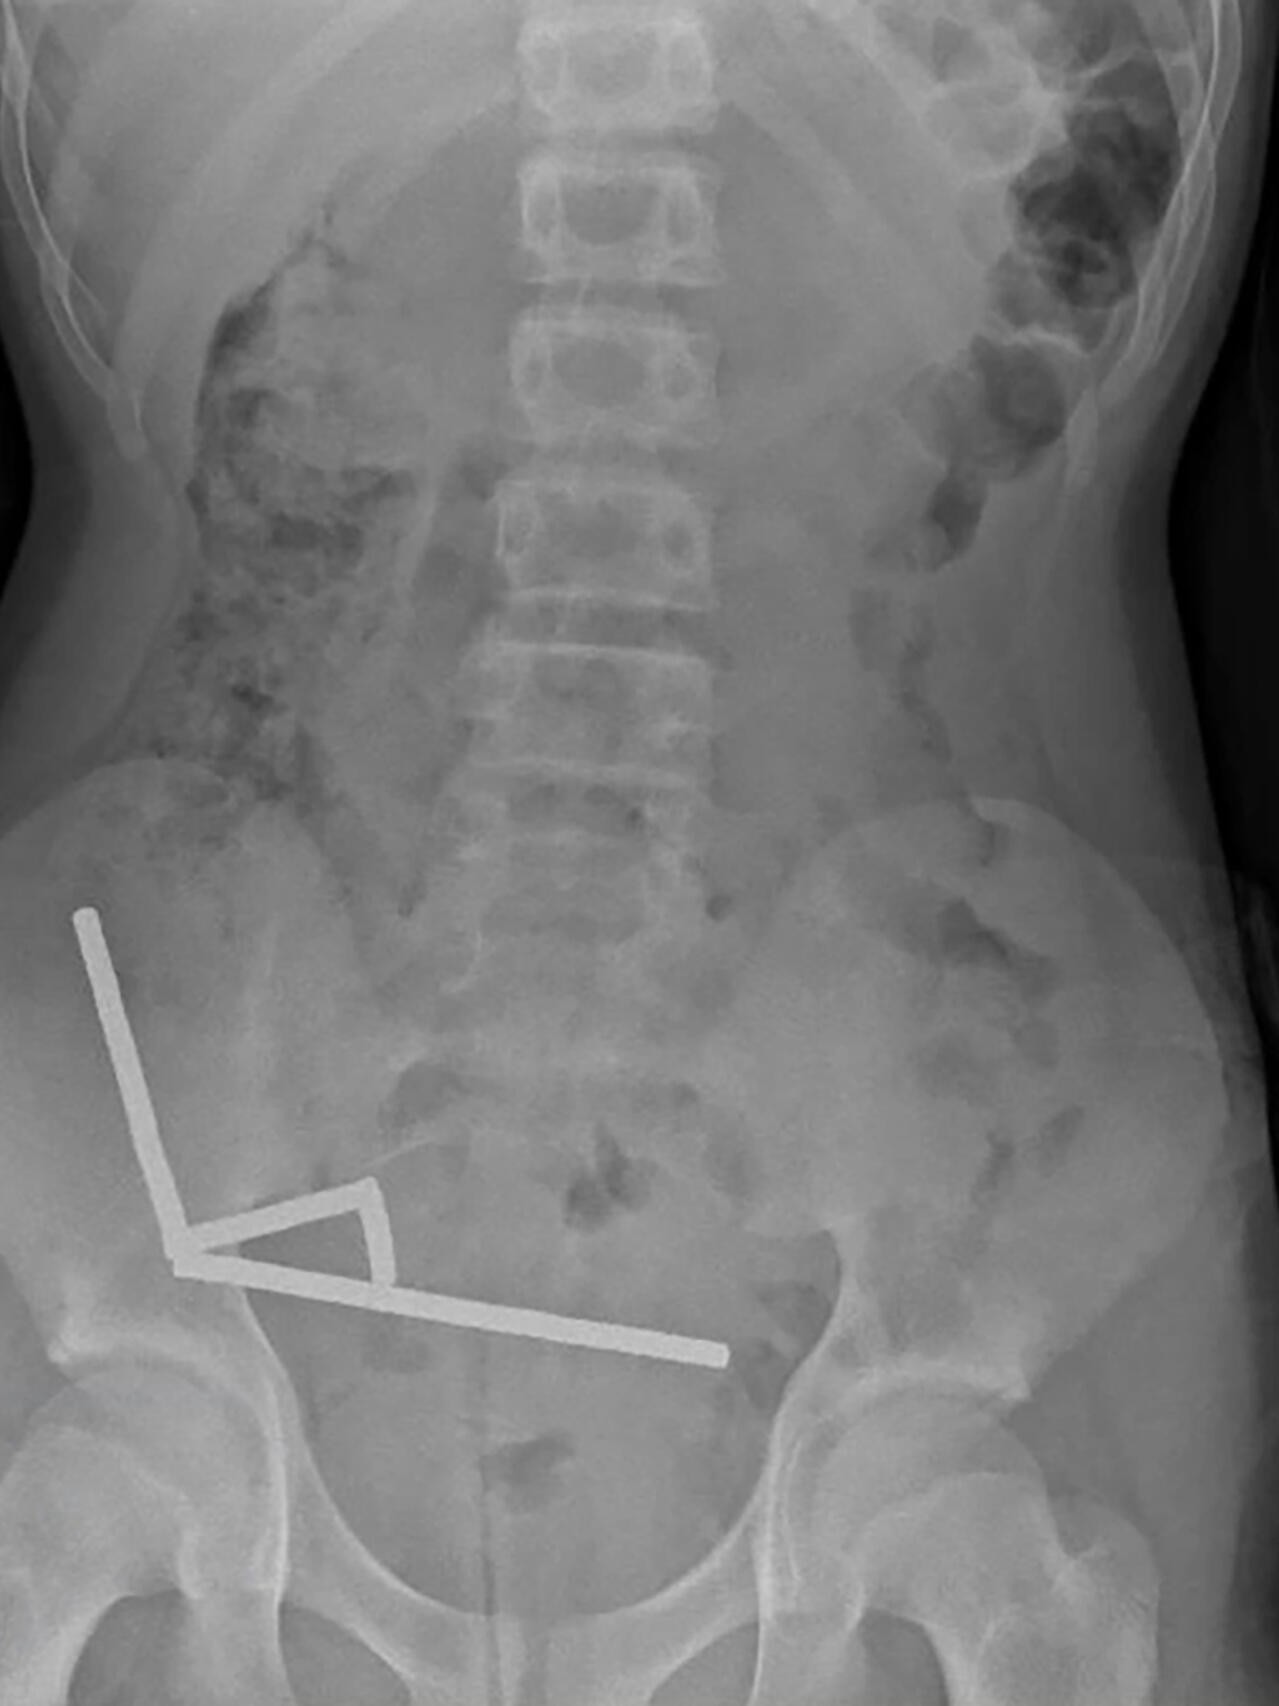

Мальчик четыре дня страдал от боли, прежде чем обратиться за медицинской помощью. Позже он признался, что около недели назад проглотил 80-100 неодимовых магнитов. Он рассказал врачам, что купил их в зарубежном интернет-магазине Temu. Рентген показал, что магниты, запрещённые в Новой Зеландии с 2013 года, образовали «четыре линейные цепочки» в кишечнике.

Врачи, подготовившие отчёт, — Бинура Лекамалаге, Люсинда Дункан-Вере и Никола Дэвис — отметили: «В ходе операции были обнаружены несколько цепочек магнитов в тонком кишечнике и слепой кишке. Они соединились в правом нижнем квадранте, сдавив ткани и вызвав некроз».